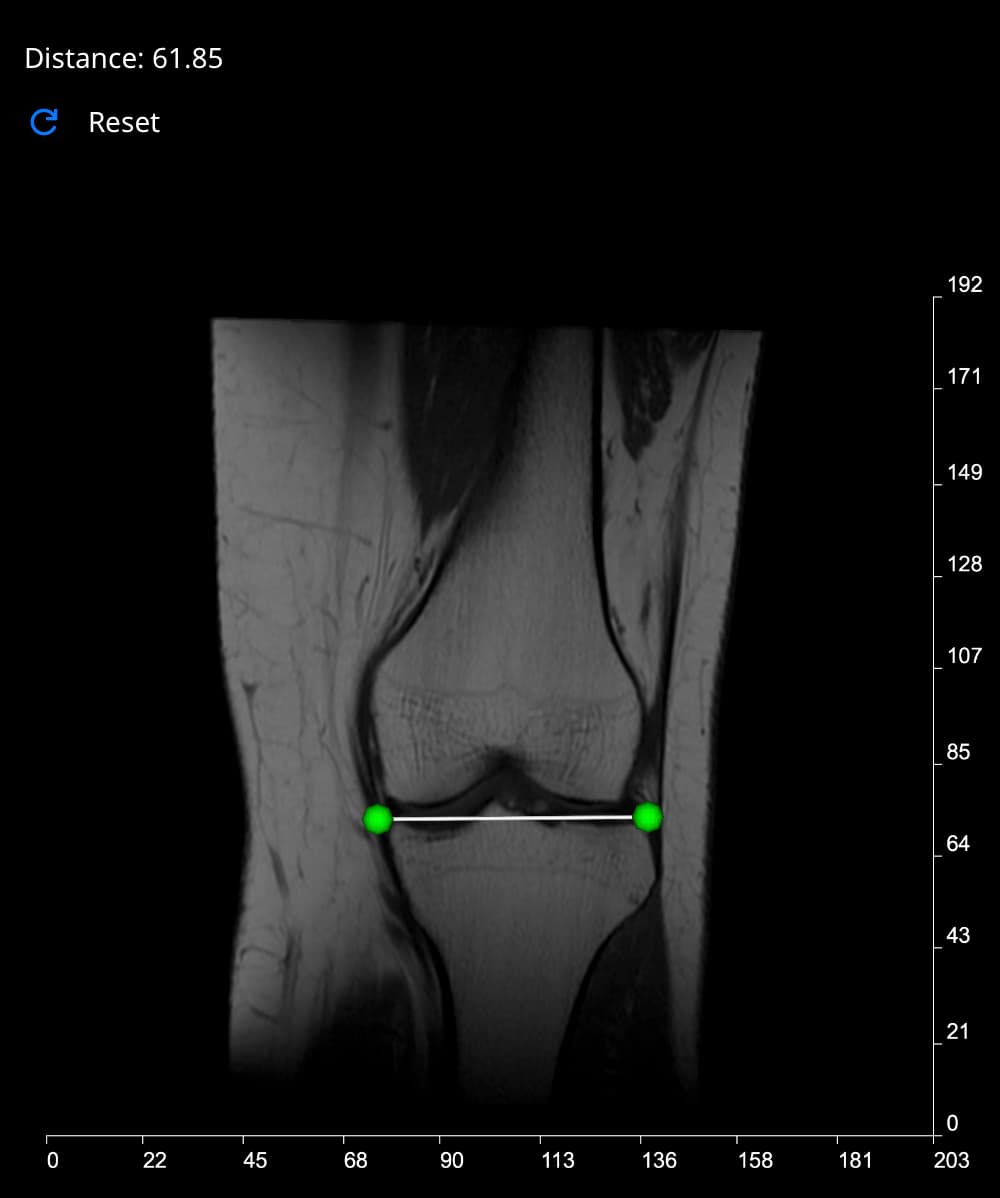

Measure Distance Tool

This tool works by following a few simple steps:

- Select the 'Measure Distance' button. Vista will reduce the opacity of the image in view by half, to enhance visibility and make your point placement more accurate.

- Move your cursor over the image, and left-click to place the first point. As you hover over the image, a blue polygon will follow your cursor. Once you place the first point, this polygon will turn green.

- As you move the cursor towards the second point, the Distance label at the top-left of the Rendering Canvas will be updated with the current distance in real time.

- Place your second point for a final reading.

If you want to start again, click the Reset button. When you are done, de-select the 'Measure Distance' button to deactivate this tool.